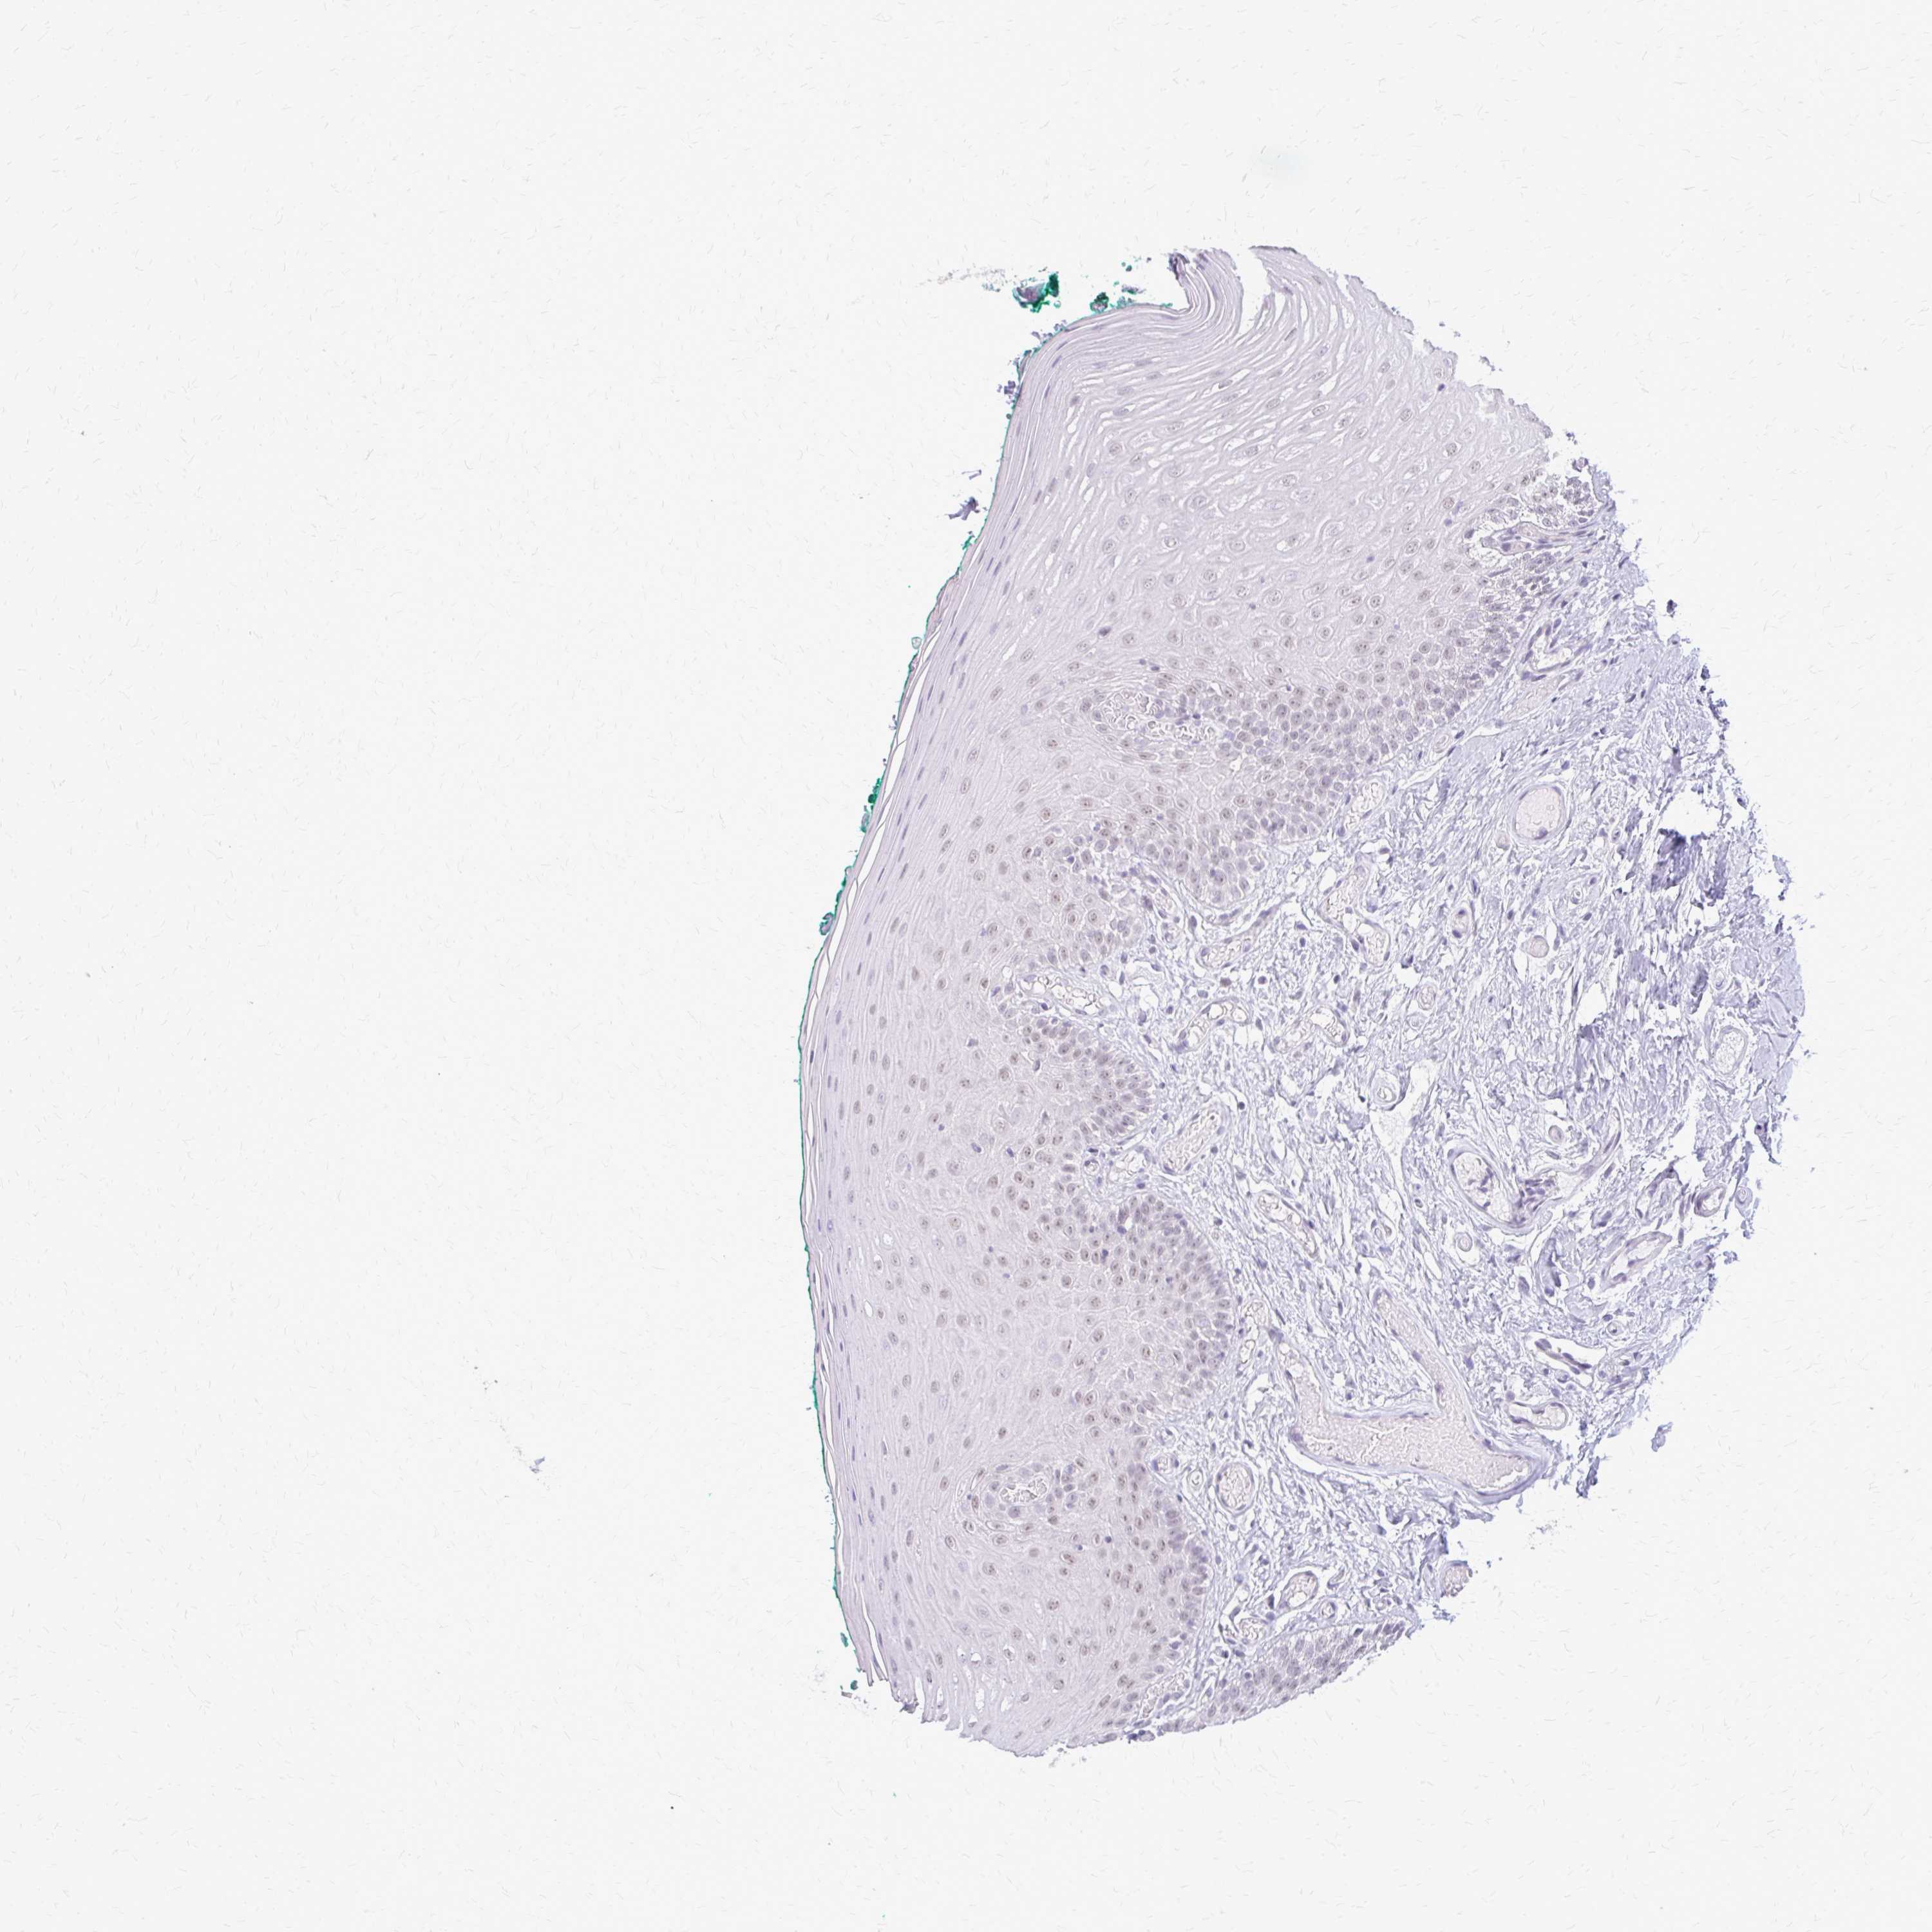

PLCB1